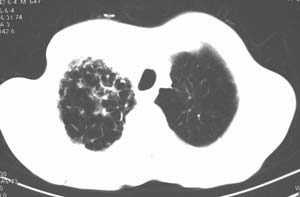

右肺上叶见片状 网格状及索条致密影.其内参杂斑点状小结节,部分融合,密度不均匀,内见含气支气管像,纵隔内见肿大淋巴结,其他肺呈代偿性肺气肿像.结合男 64  咳血,咳痰 发热 3天 血象1.2万,综合考虑:1 慢性炎症伴间质纤维化 肺气肿.2 不除外特发性感染的可能.

右肺上叶大片片状、网格状及索条致密影,前半部密实向后逐渐疏松,其内参杂斑点状小结节,密度不均匀,内见含气支气管像,纵隔内见肿大淋巴结,其他肺呈弥漫性小叶中心性性肺气肿改变,结合男 64  咳血,咳痰,发热3天,血象1.2万。考虑:1 慢性支气管炎、肺气肿合并右上肺感染。2 不除外结核合并感染的可能。

右肺上叶见片状 网格状及索条致密影.其内参杂斑点状小结节,部分融合,密度不均匀,内见含气支气管像,前段有一小片结影,纵隔内见肿大淋巴结,右侧胸腔少量积液。.结合男 64  咳血,咳痰 发热 3天 血象1.2万,综合考虑:2 右上肺感染伴间质纤维化 2 警惕细支气管肺泡癌。3建议结合临床及进一步检查[痰及纤支镜]或治疗后复查

右侧胸廓略小于左侧,右肺上叶大片实变影,近肺门处密度较高,内见支气管气相,周围较淡,呈网格状,余肺野清晰,纵隔内见肿大淋巴结,右侧胸腔少量积液。临床 咳血,咳痰 发热 , 血象1.2万。

考虑大叶性肺炎。

右侧胸阔塌陷,纵隔右移。右上肺大片状高密度影,沿支气管血管束走行,内见点状钙化;支气管充气征阳性,支气管呈柱状扩张;胸膜下小叶间隔增厚;右侧后胸壁内侧见带状水样密度影;纵隔淋巴结增大。

影像学表现:右肺上叶大片状、网格状及索条致密影,前半部密实向后逐渐疏松,其内参杂斑点状小结节,密度不均匀,内见含气支气管像,纵隔内见肿大淋巴结.